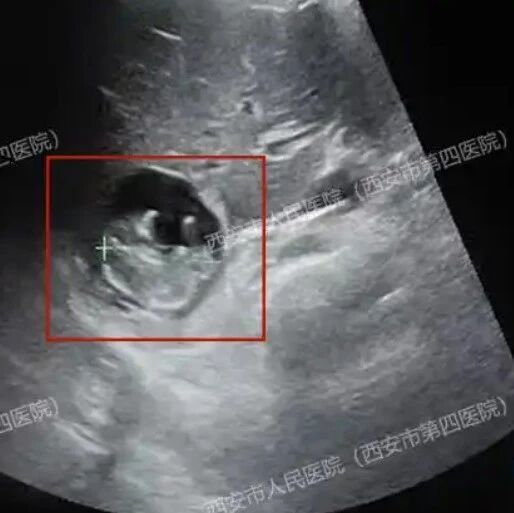

厦门新生儿医保参保报销“秒批”服务启动仪式 厦门市医保推出生育津贴“一趟不用跑”服务。 “本来都打算放弃了,没想到医保政策又给了我新的希望。”看着产检B超单上清晰的双胞胎影像,厦门市民彭女士眼泛泪光。2013年首次试管婴儿失败后,高昂的治疗费用让她一度断了生育的念头。20......